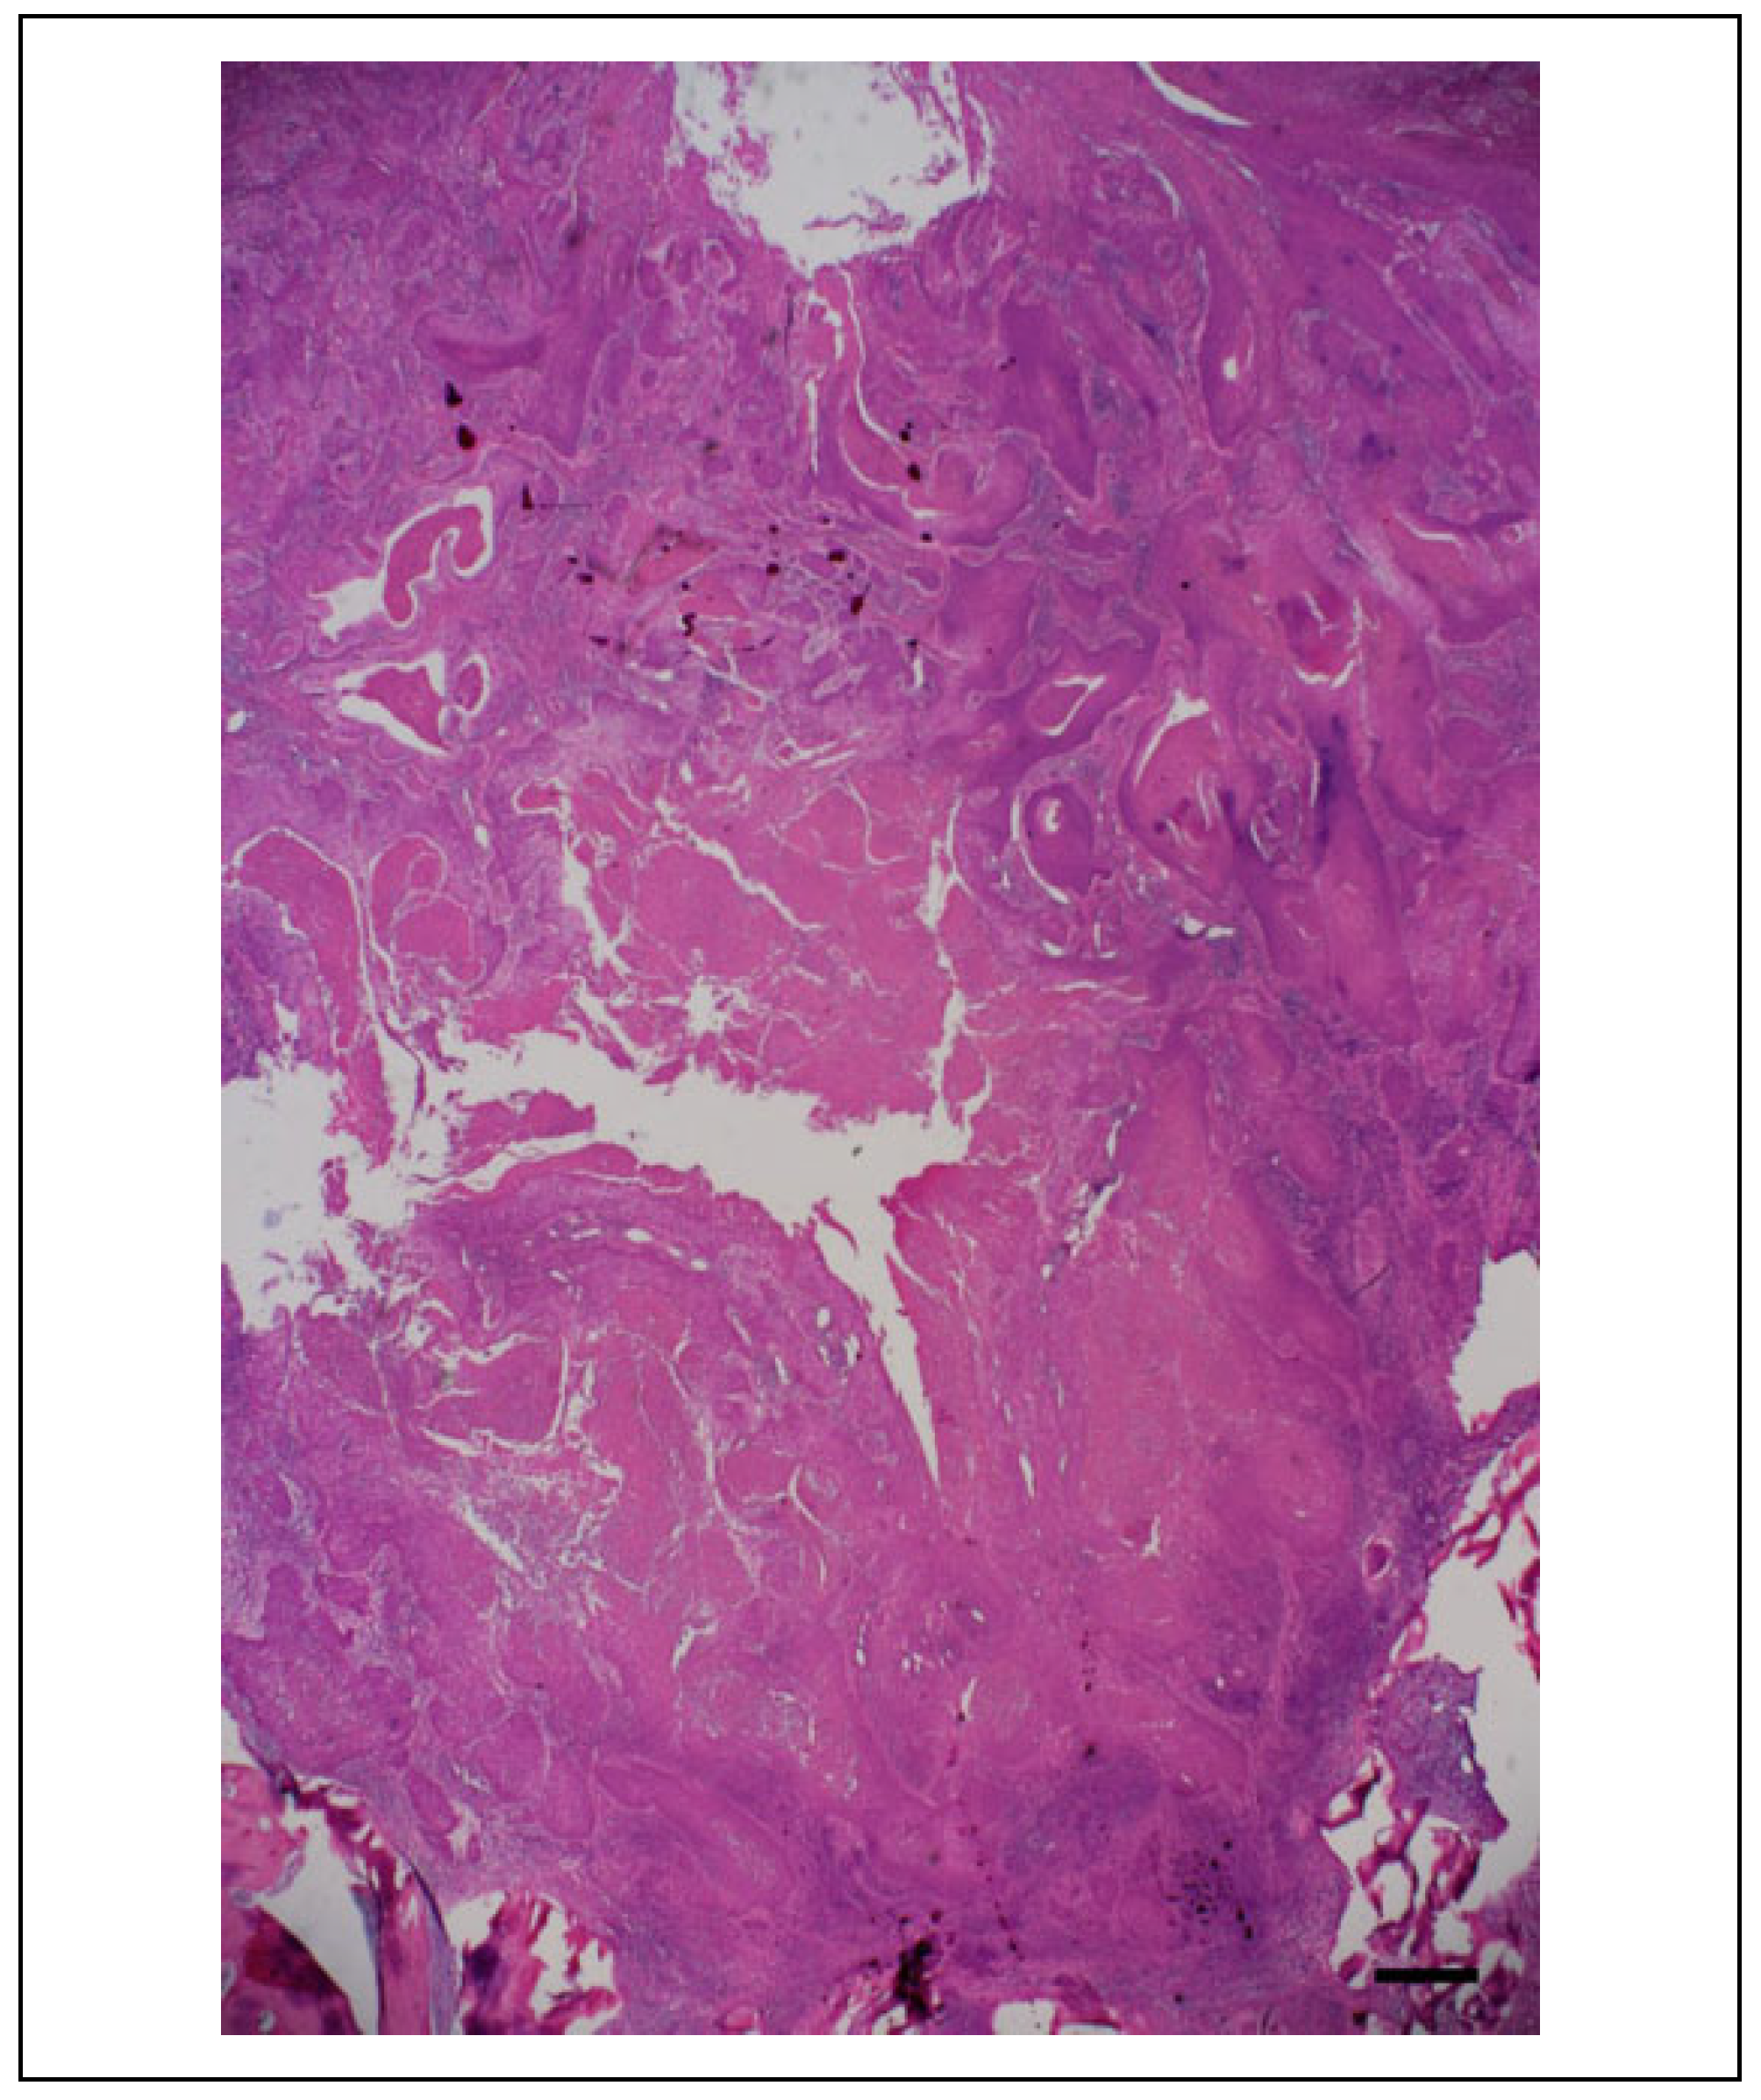

Case Presentation

Surgical Procedure

Postoperative Course